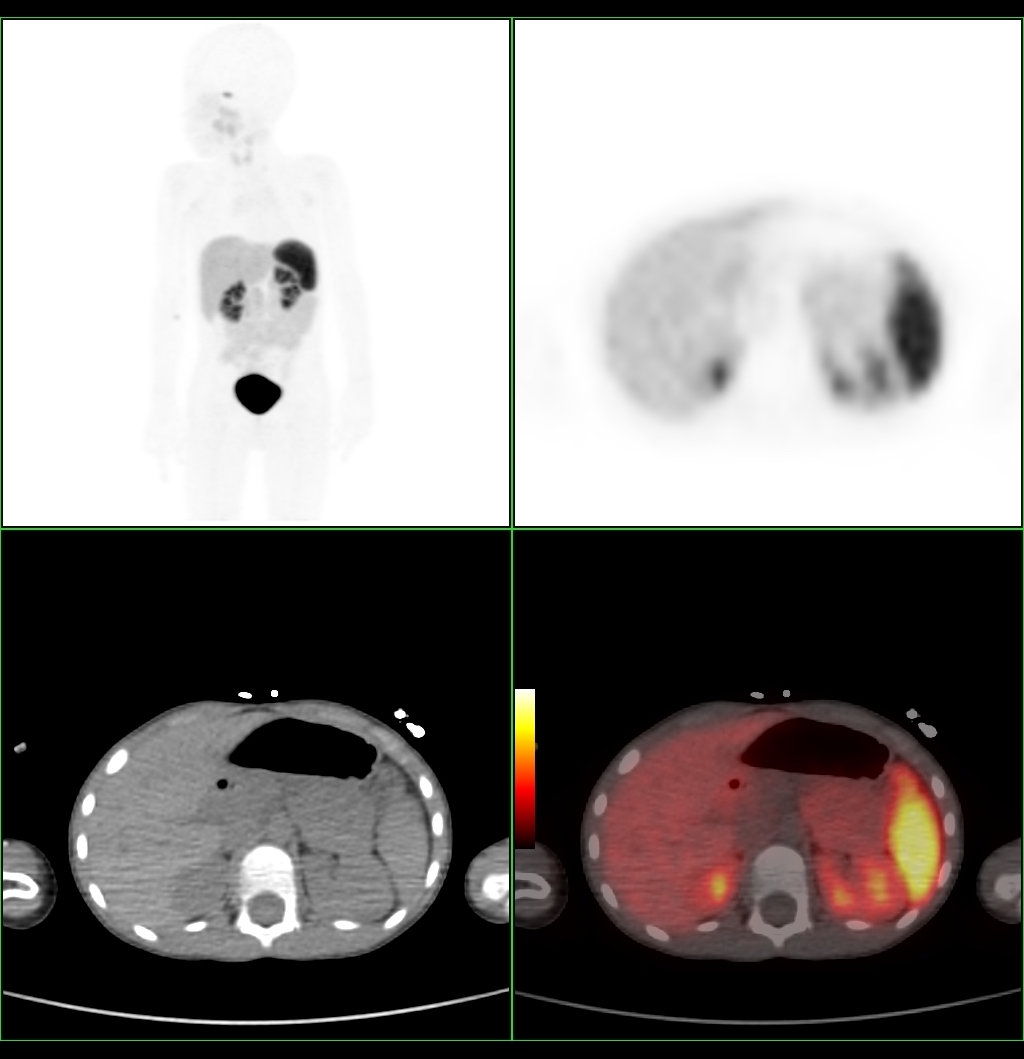

Kauno klinikose atliktas pirmasis Baltijos šalyse unikalus pozitronų emisijos tomografijos ir kompiuterinės tomografijos (PET/KT) tyrimas vaikui, sergančiam įgimtu hiperinsulinizmu, atveria naujas galimybes retų ligų diagnostikoje. Sausio mėnesį Kauno klinikų gydytojų komanda, pasitelkusi pažangiausias genetinių, molekulinių ir vaizdinimo tyrimų technologijas, penkerių metų berniukui tiksliai nustatė insulino pertekliaus šaltinį kasoje ir sudarė individualų gydymo planą.

PET/KT tyrimas, pasitelkiant specialių radiofarmacinį preparatą, leidžia gydytojams aiškiai pamatyti kasos beta ląstelių padidėjimą ir nustatyti, ar insulino pertekliaus priežastis – vienas židinys ar difuzinis pažeidimas. „Šis metodas ypatingai svarbus sprendžiant dėl chirurginio gydymo – jeigu liga židininė, galime atlikti minimaliai invazinę operaciją ir pašalinti tik pažeistą kasos dalį, taip išsaugant sveiką audinį“, – pažymi Paulius Jaruševičius, Kauno klinikų Radiologijos klinikos gydytojas radiologas.

Pirmasis Lietuvoje tokio pobūdžio tyrimas buvo atliktas berniukui, kuriam nuo kūdikystės diagnozuotas įgimtas hiperinsulinizmas. Nors gydymas buvo taikomas nuo ankstyvo amžiaus, hipoglikemijos epizodai kartojosi. Genetiniai tyrimai parodė, kad vaikas yra ABCD8 geno patogeninio varianto nešiotojas – tokiais atvejais liga paprastai nepasireiškia, todėl reikėjo papildomo tyrimo. Atliktas PET/KT tyrimas padėjo gydytojams sudaryti individualizuotą gydymo planą ir suplanuoti tolesnę berniuko priežiūrą.